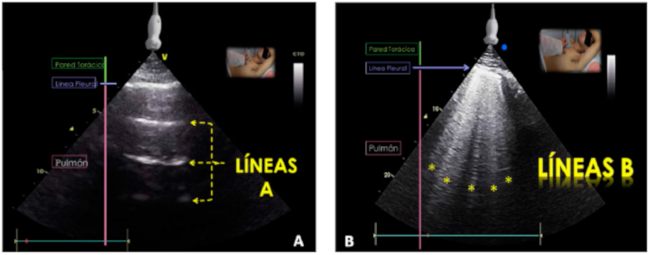

Al colocar el transductor en las regiones anteriores o superiores se obtiene la imagen de la Figura 2 A, en la cual se distingue lo siguiente:

Patrón de pulmón aireado/seco

Corresponde al 99% de aireación en el espacio pleuropulmonar y sus signos característicos son los siguientes:

“Signo del deslizamiento”.

“Signo de orilla de playa”.

Líneas A.

Cuando hay aireación del 99%, las ondas ultrasónicas que penetran la pared torácica se encuentran con la interfase línea pleural-aire, altamente reflectante y se generan artefactos de reverberación de la línea pleural llamados “líneas A”, que son horizontales, paralelas a la línea pleural, se desvanecen en la profundidad y son equidistantes al espacio entre la piel y la línea pleural. En este patrón, el espacio subpleural se presenta como un área hipoecoica con líneas A. Corresponde a pulmones normales o con patologías con atrapamiento aéreo como EPOC y asma (Figura 3 A).

Patrón de pulmón húmedo, patrón intersticial o síndrome intersticial

Se presenta con aireación de un 95%-97% (3%-5% de líquido) y se caracteriza por la presencia de líneas B (Figura 3 B). En el pulmón, el líquido se acumula inicialmente en el espacio intersticial, (septos interlobulillares e intralobulillares rodeados de alvéolos). La onda ultrasónica interacciona con la interfase línea pleural-fluido intersticial (líquido o citoplasma de células inflamatorias), que permite la transmisión de la onda hasta el espacio intersticial donde al encontrarse con el aire alveolar se refleja y queda atrapada entre dos interfaces reflectantes línea pleural - aire alveolar y se generan artefactos denominados “líneas B”, que presentan 6 características:

Artefactos verticales.

Inician en la línea pleural.

Llegan hasta el final de la pantalla.

Tienen aspecto de rayos láser.

Ocultan las líneas A a su paso.

Son dinámicas, se mueven con el deslizamiento pleural.

Pueden presentarse normalmente en número menor de 3 predominantemente en las regiones más declives del tórax. Sin embargo, la presencia de 3 o más líneas B en un espacio intercostal por abordaje longitudinal, se denomina patrón intersticial, término acuñado por Lichtenstein en 1997. 10